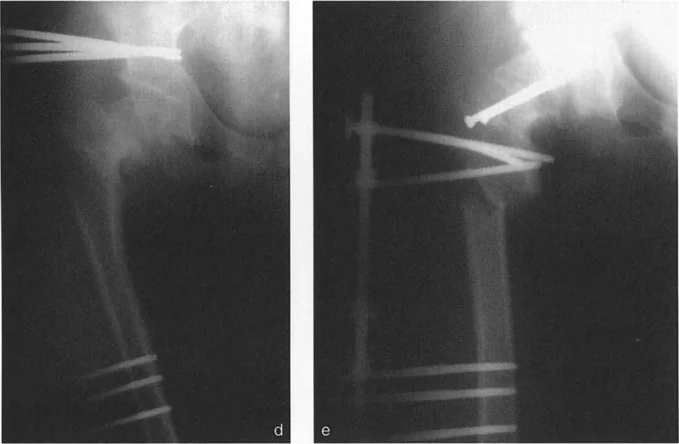

التدخل الجراحي: قطع العظم (Osteotomy)

عندما تفشل العلاجات التحفظية في تخفيف الأعراض أو عندما يكون التشوه شديدًا ويُهدد وظيفة المفصل على المدى الطويل، يُصبح التدخل الجراحي ضروريًا. تُعد عملية قطع العظم (Osteotomy) إجراءً جراحيًا يتم فيه قطع العظم وإعادة تشكيله لتصحيح التشوه وإعادة محاذاة المفصل. يُطبق الأستاذ الدكتور محمد هطيف مبادئ بالي (Paley's Principles) بدقة متناهية لضمان تصحيح مثالي وتجنب المضاعفات.

تنفيذ قطع العظم في المستوى السهمي

تُعالج التشوهات العظمية المصحوبة بأعراض في الجزء القريب من عظم الفخذ والتي تفشل في الاستجابة للعلاج التحفظي عن طريق قطع العظم التصحيحي. يجب أن تتبع عمليات قطع العظم هذه بشكل صارم قواعد بالي لتصحيح التشوهات الزاوية لتجنب إحداث انحرافات ميكانيكية المنشأ.

تطبيق مبادئ بالي على جراحة الورك

يُعد فهم العلاقة بين مركز دوران الانحراف (CORA) ومستوى قطع العظم أمرًا بالغ الأهمية.

- قاعدة قطع العظم 1: إذا تم إجراء قطع العظم بالضبط عند مستوى CORA، فإن تصحيحًا زاويًا فقط (بفتح أو إغلاق وتد) يكون مطلوبًا. يتم استعادة المحور الميكانيكي، ولن يحدث أي إزاحة لقطعي العظم.

- قاعدة قطع العظم 2: إذا كان CORA يقع قريبًا (أو بعيدًا) عن المستوى الفعلي لقطع العظم، فيجب إزاحة الجزء البعيد لاستعادة المحور الميكانيكي. سيؤدي التقويم الزاوي البحت عند مستوى بعيد عن CORA إلى تشوه إزاحة ثانوي.

في الجزء القريب من عظم الفخذ، غالبًا ما يقع CORA لتشوه سهمي في الجزء العلوي من عنق الفخذ أو حتى داخل رأس الفخذ. ومع ذلك، لأسباب تتعلق بالشفاء البيولوجي وتثبيت الأجهزة، غالبًا ما يتم إجراء قطع العظم في مستوى أدنى بكثير، عادة في منطقة ما بين المدورين أو تحت المدور.

نظرًا لأن CORA يقع قريبًا من خط قطع العظم، فإن الإزاحة إلزامية تمامًا أثناء التصحيح:

* لتشوهات الانبساط (التي تتطلب قطع عظم للانثناء): يجب إزاحة عمود الفخذ للأمام.

* لتشوهات الانثناء (التي تتطلب قطع عظم للانبساط): يجب إزاحة عمود الفخذ للخلف.

سيؤدي الفشل في إزاحة عمود الفخذ بشكل مناسب إلى تشوه إزاحة ثانوي، مما يُغير المحور الميكانيكي للطرف السفلي (انحراف المحور الميكانيكي - MAD) وقد يسبب ميلان خط المفصل عند الركبة.